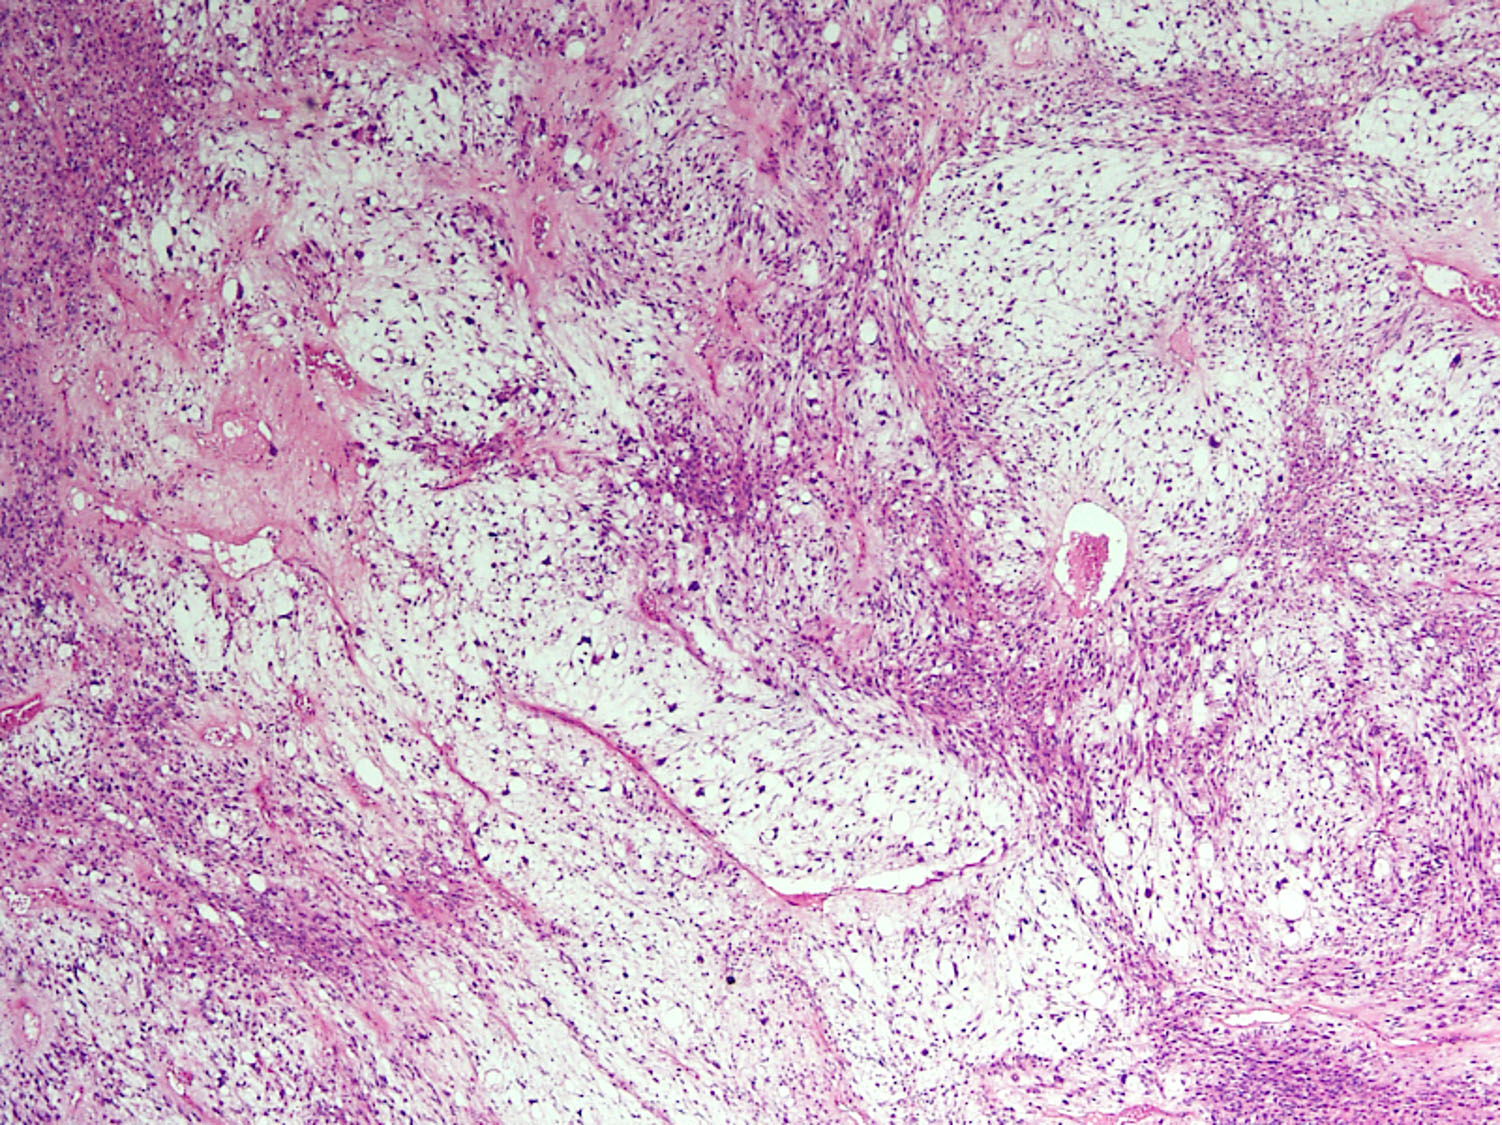

1)Fascéite nodulaire

Accolé à un fascia (bande éosinophile) mais parfois dans le derme

Espaces myxoïdes et kystiques, parfois collagénique

Prolifération myofibroblastique : tissue culture avec aspect de tissu de granulation

Pas de pléomorphisme (parfois on retrouve des cellules ganglionaire like (photo)

Erythrocytes extravasés

Fibres musculaires disséquées

4)

SMA+, DES-,Caldesmon

5) MYH9-USP6